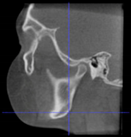

Three points determined the Acta plane: O, F right (FR), and F left (FL) (Table 2). Point O is the midpoint between the most craniodorsal point of the dorsum Sella and the most posterior dorsal point of the Basion in the midsagittal plane (Figure 1). Both points F are a result of the intersection between two lines: the line that connects the most inferior points of the lower orbital margins, right and left, and a line perpendicular to this line that runs through the most external points of the orbital margins, right and left (Figure 2). The new transverse reference plane, the Acta plane (Figure 2), is created by connecting the O-point (Figure 1) with FR and FL (Figure 2).

Figure 1.

Point O (green dot) is the midpoint between the dorsum Sella (Se) (red dot) and the Basion point (Ba) (yellow dot).

When determining the internal reference of the skull, the aim was to determine an origin point in the midsagittal plane, as previous studies have confirmed the consistency of the landmarks in the midsagittal plane [17,34]. At first, the midpoint between the left and right anterior clinoid processes was considered as the origin point. However, the left and right anterior clinoid processes have been reported as a reference with low reliability [35], and they were asymmetric in dry skulls as well as in many CBCT images from this sample. The second option was to use the most anterior border of the dorsum Sella. However, the Sella landmarks (Sella, Sella inferior, Sella posterior) are highly dependent on the DICOM orientation [17,35,36]. On the other hand, the most superior-posterior point of the dorsum Sella seemed more accessible and less orientation-dependent on the CBCT images. However, after using this point to align the CBCT scans, the final head position rolled too far backward. This issue was probably caused by the excessively high position of the dorsum Sella relative to the F-points. To address this discrepancy, the origin point was set in a lower position. One of the options considered was the Basion point. However, its position was too low in regard to the F points, which resulted in a forward-rolled skull after reorientation. As a result, the midpoint between the Basion and the dorsum Sella was adopted as the origin point, named point O.